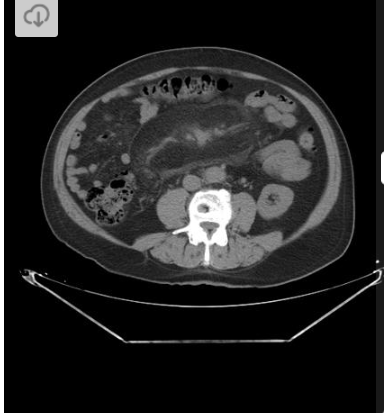

Homem, 45 anos, Dor abdominal, distensão e parada da eliminação de fezes e flatos.

Hérnia interna - pericecal.

Causa de obstrução intestinal de delgado.

Segundo tipo mais comum de hérnia interna, perdendo para a paraduodenal.

A alça herniada geralmente consiste em um segmento ileal que se projeta através de um defeito no mesentério cecal (que pode ser congênito ou adquirido)